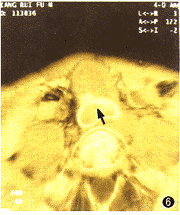

主动脉假性动脉瘤3例。CTVE表现为动脉管壁于某处突然中断,在中断处有一裂隙与周围一不规则形大腔相通,同时仍可看到正常的动脉管腔(图4~6)。

图4~6 主动脉假性动脉瘤。图4为多平面重建法(MPR)图像,示胸主动脉假性动脉瘤。图5为CTVE图像,示正常降主动脉、裂口、假腔。图6为CTVE图像,示腹主动脉假性动脉瘤裂

3.主动脉假性动脉瘤:可发现动脉壁破裂的位置、裂口形态及长度等, 这是现有的其他检查手段所无法做到的。本组病例中,3例假性动脉瘤均发现了破口位置,为临床提供了强有力的依据。值得一提的是,为我院1例高难度腔内隔绝术治疗巨大腹腔干假性动脉瘤的手术提供了极有价值的信息,保证了手术的成功,是其他检查手段无法取代的。